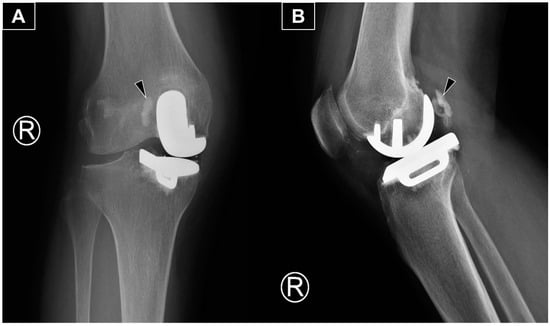

Figure 1.

The anteroposterior (A) and lateral (B) radiographs reveal the main portion of the extruded cement (arrowhead) positioned posterolateral to the medial femoral metallic component. The radiograph is from a 66-year-old woman with isolated medial compartment osteoarthritis of the right knee who experienced mechanical knee pain, with a visual analog scale (VAS) score of 7/10. Her symptoms had limited her walking to 30 min with the assistance of a walking stick. She could ascend only one flight of stairs (using a stick and rail support) and was unable to squat due to knee pain and stiffness. After exhausting all non-operative treatments without significant improvement, she underwent a medial uni-compartmental knee replacement. She first presented to our clinic three months postoperatively with persistent knee swelling and posterior knee pain during deep flexion. She was afebrile and ambulated with a walking stick, though with some difficulty. Examination revealed moderate knee swelling with mild warmth and tenderness but no erythema. The surgical wound was well-healed. Active knee extension was complete, and flexion reached 100 degrees actively and 120 degrees passively, with posterior knee tenderness at the end range of flexion. Ligamentous stability was intact, and no posterior swelling or skin changes were observed. There was no calf swelling or other leg symptoms, and the neurovascular examination was normal. Radiographs showed an opacity posterior to the metallic femoral component, consistent with extruded cement from the fixation.